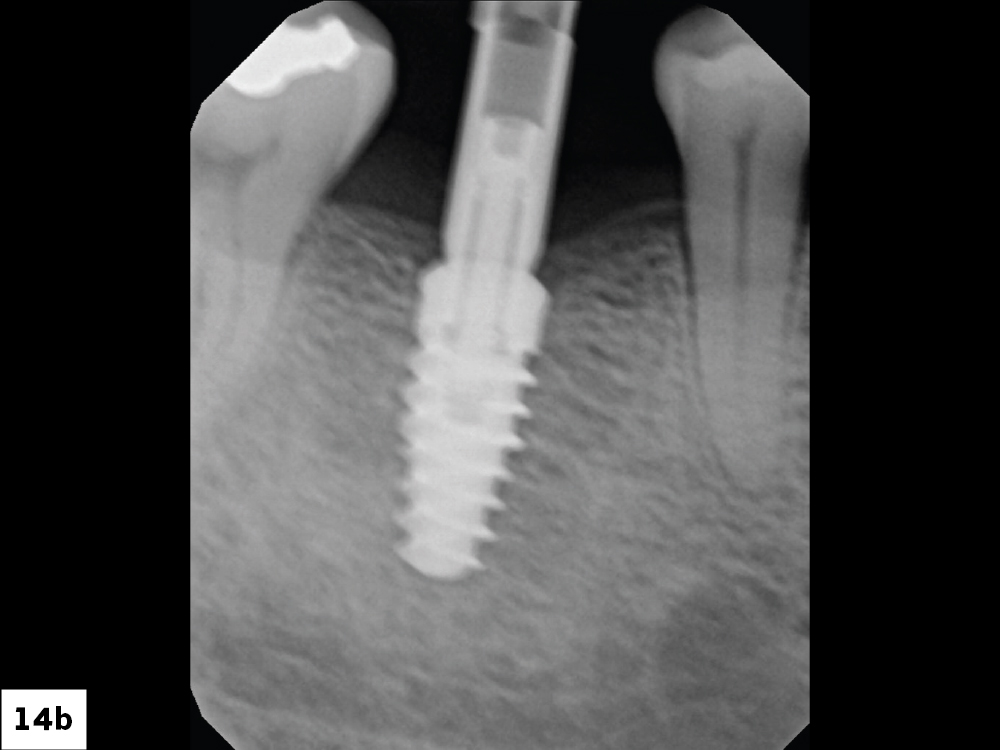

Glidewell HT Implant Titanium Scan Body Placement

Radiograph to Confirm Proper Seating of Scan Body

Figures 14a, 14b: A Glidewell HT Implant Titanium Scan Body (Glidewell Direct) was placed, and proper seating was confirmed with a radiograph. Completely seating the scan body is important. If the scan body is not properly seated, the final restoration will not seat either. Make sure the scan body is screwed into the implant connection and hand-tightened.